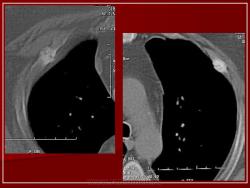

Выглядят как рахитические четки. Может, с-м Титце?

Вероятно это перестройки в ребрах по типу Дойчлендера...

Банальные переломы?

Вот у ребенка рахитические четки, очень похожие изменения.

Прекрасное наблюдение Ольга, но, увы, на радиографии. Но, в Вашем наблюдении ребенок, а в представленном случае довольно зрело-перезрелый фрукт.

Кстати, а разве с-м Титце - это не патологическая перестройка? Вроде у Рейнберга это и имеется ввиду.